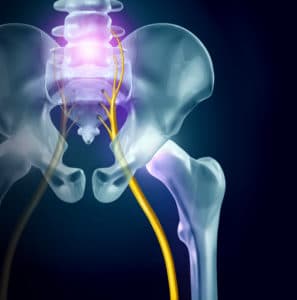

Sciatica is a term used to describe pain and other symptoms caused by irritation or compression of the sciatic nerve. The sciatic nerve is the largest nerve in the body, traveling from the lower spine through the buttocks and down each leg to the feet and toes. It controls muscles in the legs and provides sensation to much of the lower extremities. When this nerve becomes compressed, symptoms can range from mild discomfort to significant mobility limitations.

Sciatica is not a diagnosis itself but a description of symptoms that occur when one or more of the nerve roots forming the sciatic nerve are compressed. This compression usually happens in the lumbar spine before the nerve roots join together.